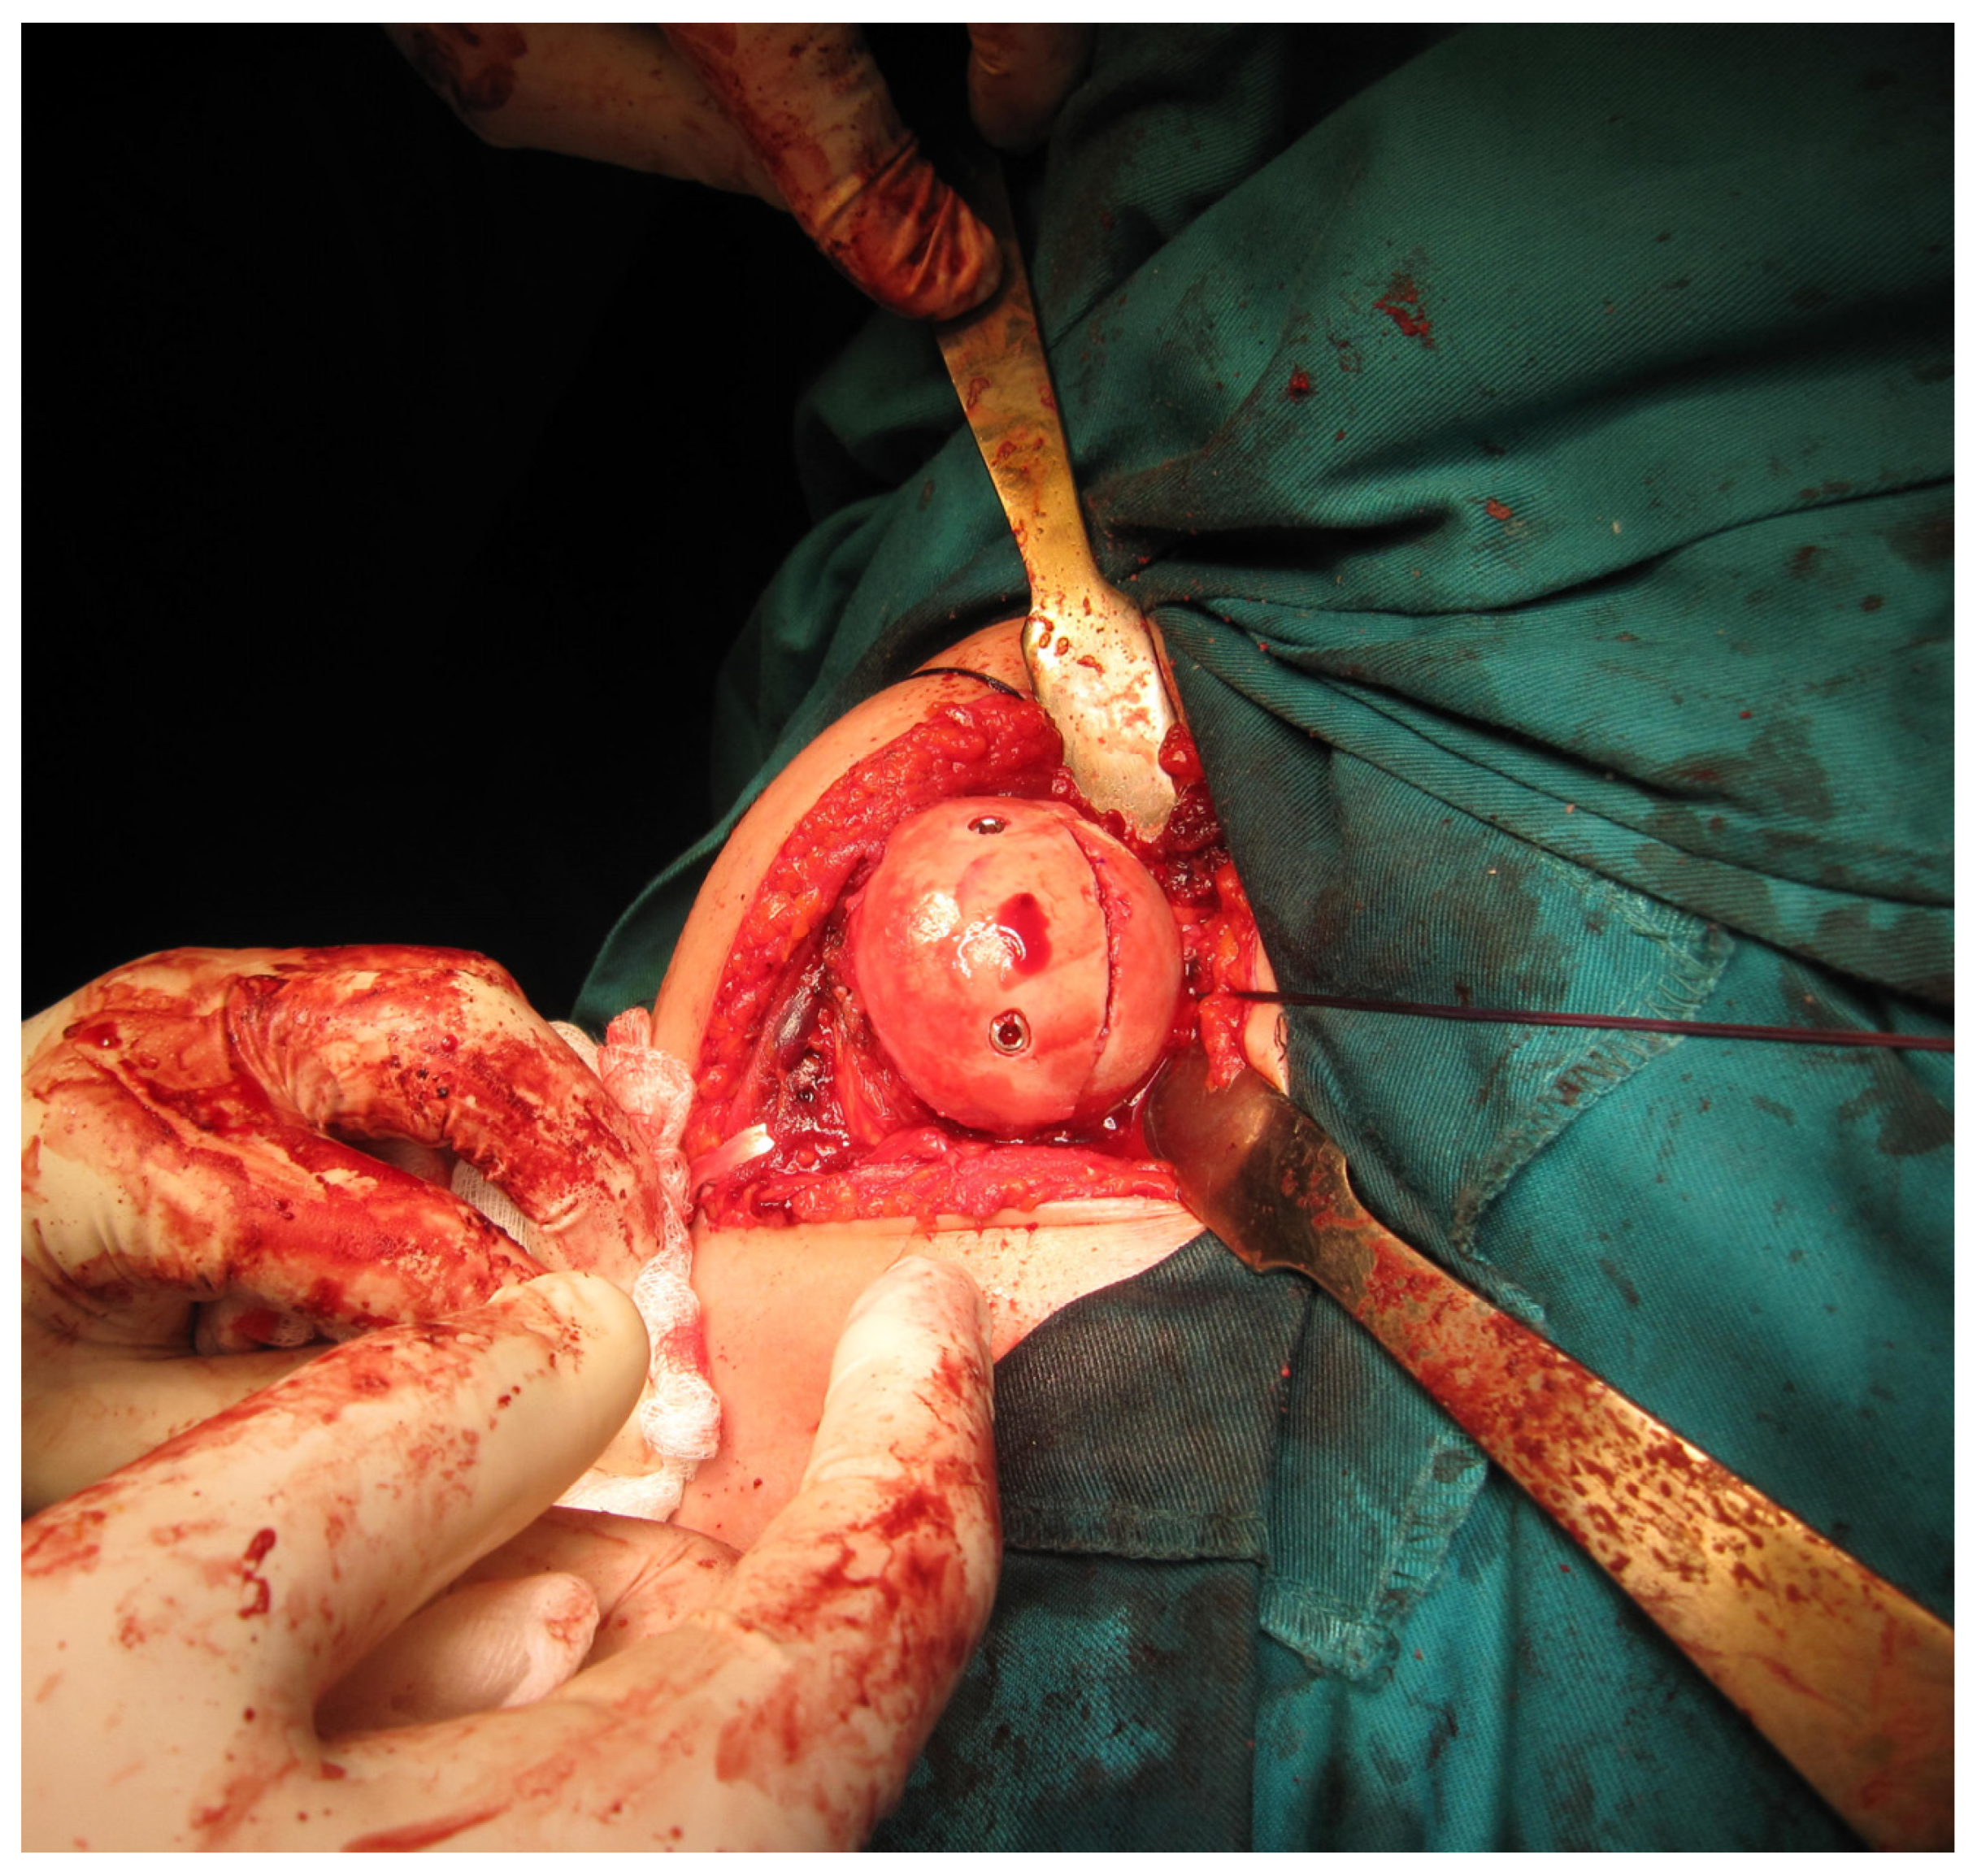

All femoral condyle osteochondral allografts were fresh-frozen and stored at −80 °C. They were tested for bacterial contamination, as well as serologically for hepatitis (A, B and C) and human immunodeficiency virus. On the day of surgery, the osteochondral grafts were thawed and submerged in 300 mL of saline solution with five ampoules of 120 mg gentamycin. Before placement, the grafts were washed with 500 mL of pure physiological solution. An oscillating saw was used to prepare the humeral head defect site for the osteochondral allograft. The dimensions of the lesion were carefully measured, and a similarly sized allograft was modeled accordingly (Figure 2 and Figure 3). Tenodesis of the long head of the bicep tendon was performed in all patients. Fixation of the allograft to the humeral head was achieved using two cancellous screws in four patients, while two Herbert screws [8] were used in the remaining sixteen patients, all placed subchondrally (Figure 4). After the shoulder joint was reduced into place, the reinsertion of the m. subscapularis was performed in its anatomical position (because osteotomy of the lesser tubercle was performed during the procedure). During the immobilization period, the m. subscapularis healed in its anatomical position. The shoulder joint capsule was sutured with absorbable sutures and the wound was closed in layers.

Figure 3. Osteochondral femoral allograft (photo from the personal archive of intraoperative photos of the author).